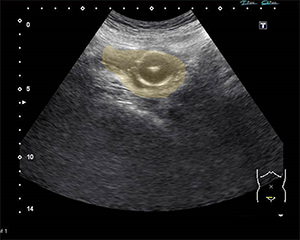

カテーテル交換後にエコーで膀胱内の固定バルーン(写真1)を確認できれば、尿の流出がなくても一安心です。また、膀胱留置カテーテル管理中に尿量が激減した際、原因が無尿なのかカテーテルの屈曲や閉塞なのかについて迷うことがあります。そのようなときは、エコーで膀胱内を観察すれば、緊急受診の必要性を判断できます。

写真1 膀胱留置カテーテル固定バルーンの確認

膀胱(オレンジの範囲)内に固定バルーンがある状態